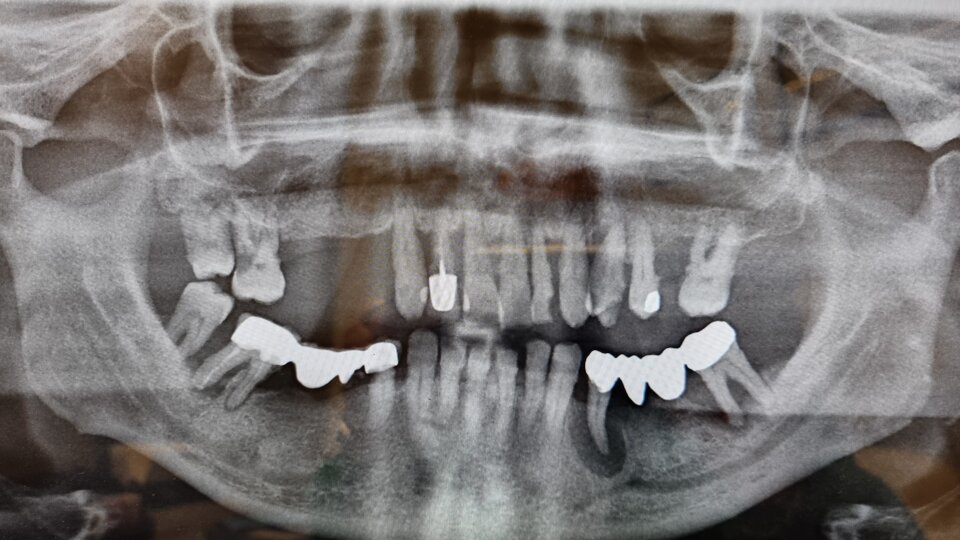

VL'implantologia è la branca più giovane dell'odontoiatria e si occupa della sostituzione dei denti persi o ancora da estrarre utilizzando viti in titanio, più raramente lame intraossee o reti da appoggiare sull'osso ( in questo caso si parla di tecnica iuxta ossea o sottoperiostea).

Parliamo di MONO IMPIANTO quando il dente da sostituire è uno solo e di full arch quando è coinvolta una intera arcata dentale.

La tecnica più usata al giorno d'oggi si chiama ALL ON FOUR oppure ALL ON SIX e prevede la realizzazione di una intera arcata composta di dodici ( più raramente quattordici) denti fissi montati su una barra in titanio che verrà fissata su 4 o 6 impianti inseriti nell'osso ( da cui il nome).

QUI SOTTO UN ESEMPIO DI ALL ON FOUR DEFINITIVA A CARICO IMMEDIATO REALIZZATA NELLO STESSO GIORNO